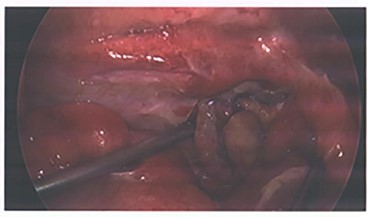

Due to the embolization of an end artery, the high possibility of ischaemia of the appendix was a concern and the patient was closely monitored for signs of rebleeding and peritonism. He was also prophylactically placed on IV antibiotics per trust guidelines for intra-abdominal pathology. After 72 hours of conservative management, he exhibited signs of local peritonism in the right iliac fossa and a rising white cell count and the decision was made to proceed with operative management. A laparoscopic appendicecetomy was performed, and he was found to have an inflamed appendix with blue discoloration indicating ischemia (Fig. 3). No perforation or other abnormalities throughout the examined bowel were identified. Final histology demonstrated partial distal infarction, healthy viable base and no sign of neoplasm. The patient had an unremarkable recovery following his operation and was discharged after 2 days.

Images from angiography. (A) Pre-embolization, demonstrates appendiceal lumen filled with contrast. (B) Demonstrated coiled artery.